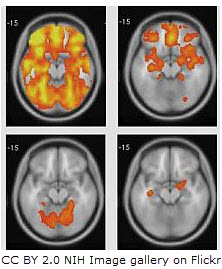

![]() | The Cerebral cortexTime 1 hour This is an activity containing five short tasks which cover the important points about the cerebral cortex, its structure and function, the specific functions of those named areas named in the IB guide and some of the methods biologists have used to work out how the brain works. This is an exciting area of Biology which is advancing very rapidly. | |